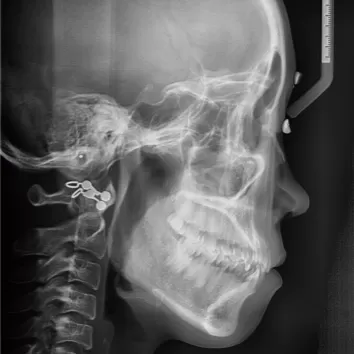

X-rays before treatment

[Panoramic Radiography/Lateral Cephalogram]